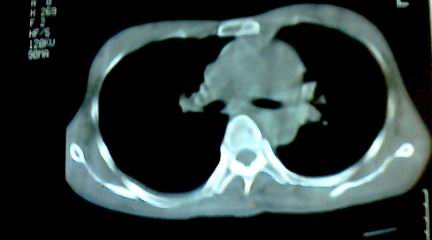

标题: CT25218:请教!胸部CT,胸8椎体骨质破坏,伴周围软组织肿。 [打印本页]

标题: CT25218:请教!胸部CT,胸8椎体骨质破坏,伴周围软组织肿。

患者,女41岁,肢体乏力。

两肺上叶继发性肺结核;胸椎结核并椎旁寒性脓肿形成。

两肺上叶继发性肺结核;胸椎结核并椎旁寒性脓肿形成

恶性,椎体淋巴瘤或pnet并肺内转移。